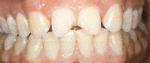

Boventanden vóór de behandeling met composiet.

Dezelfde tanden ná de behandeling met composiet.